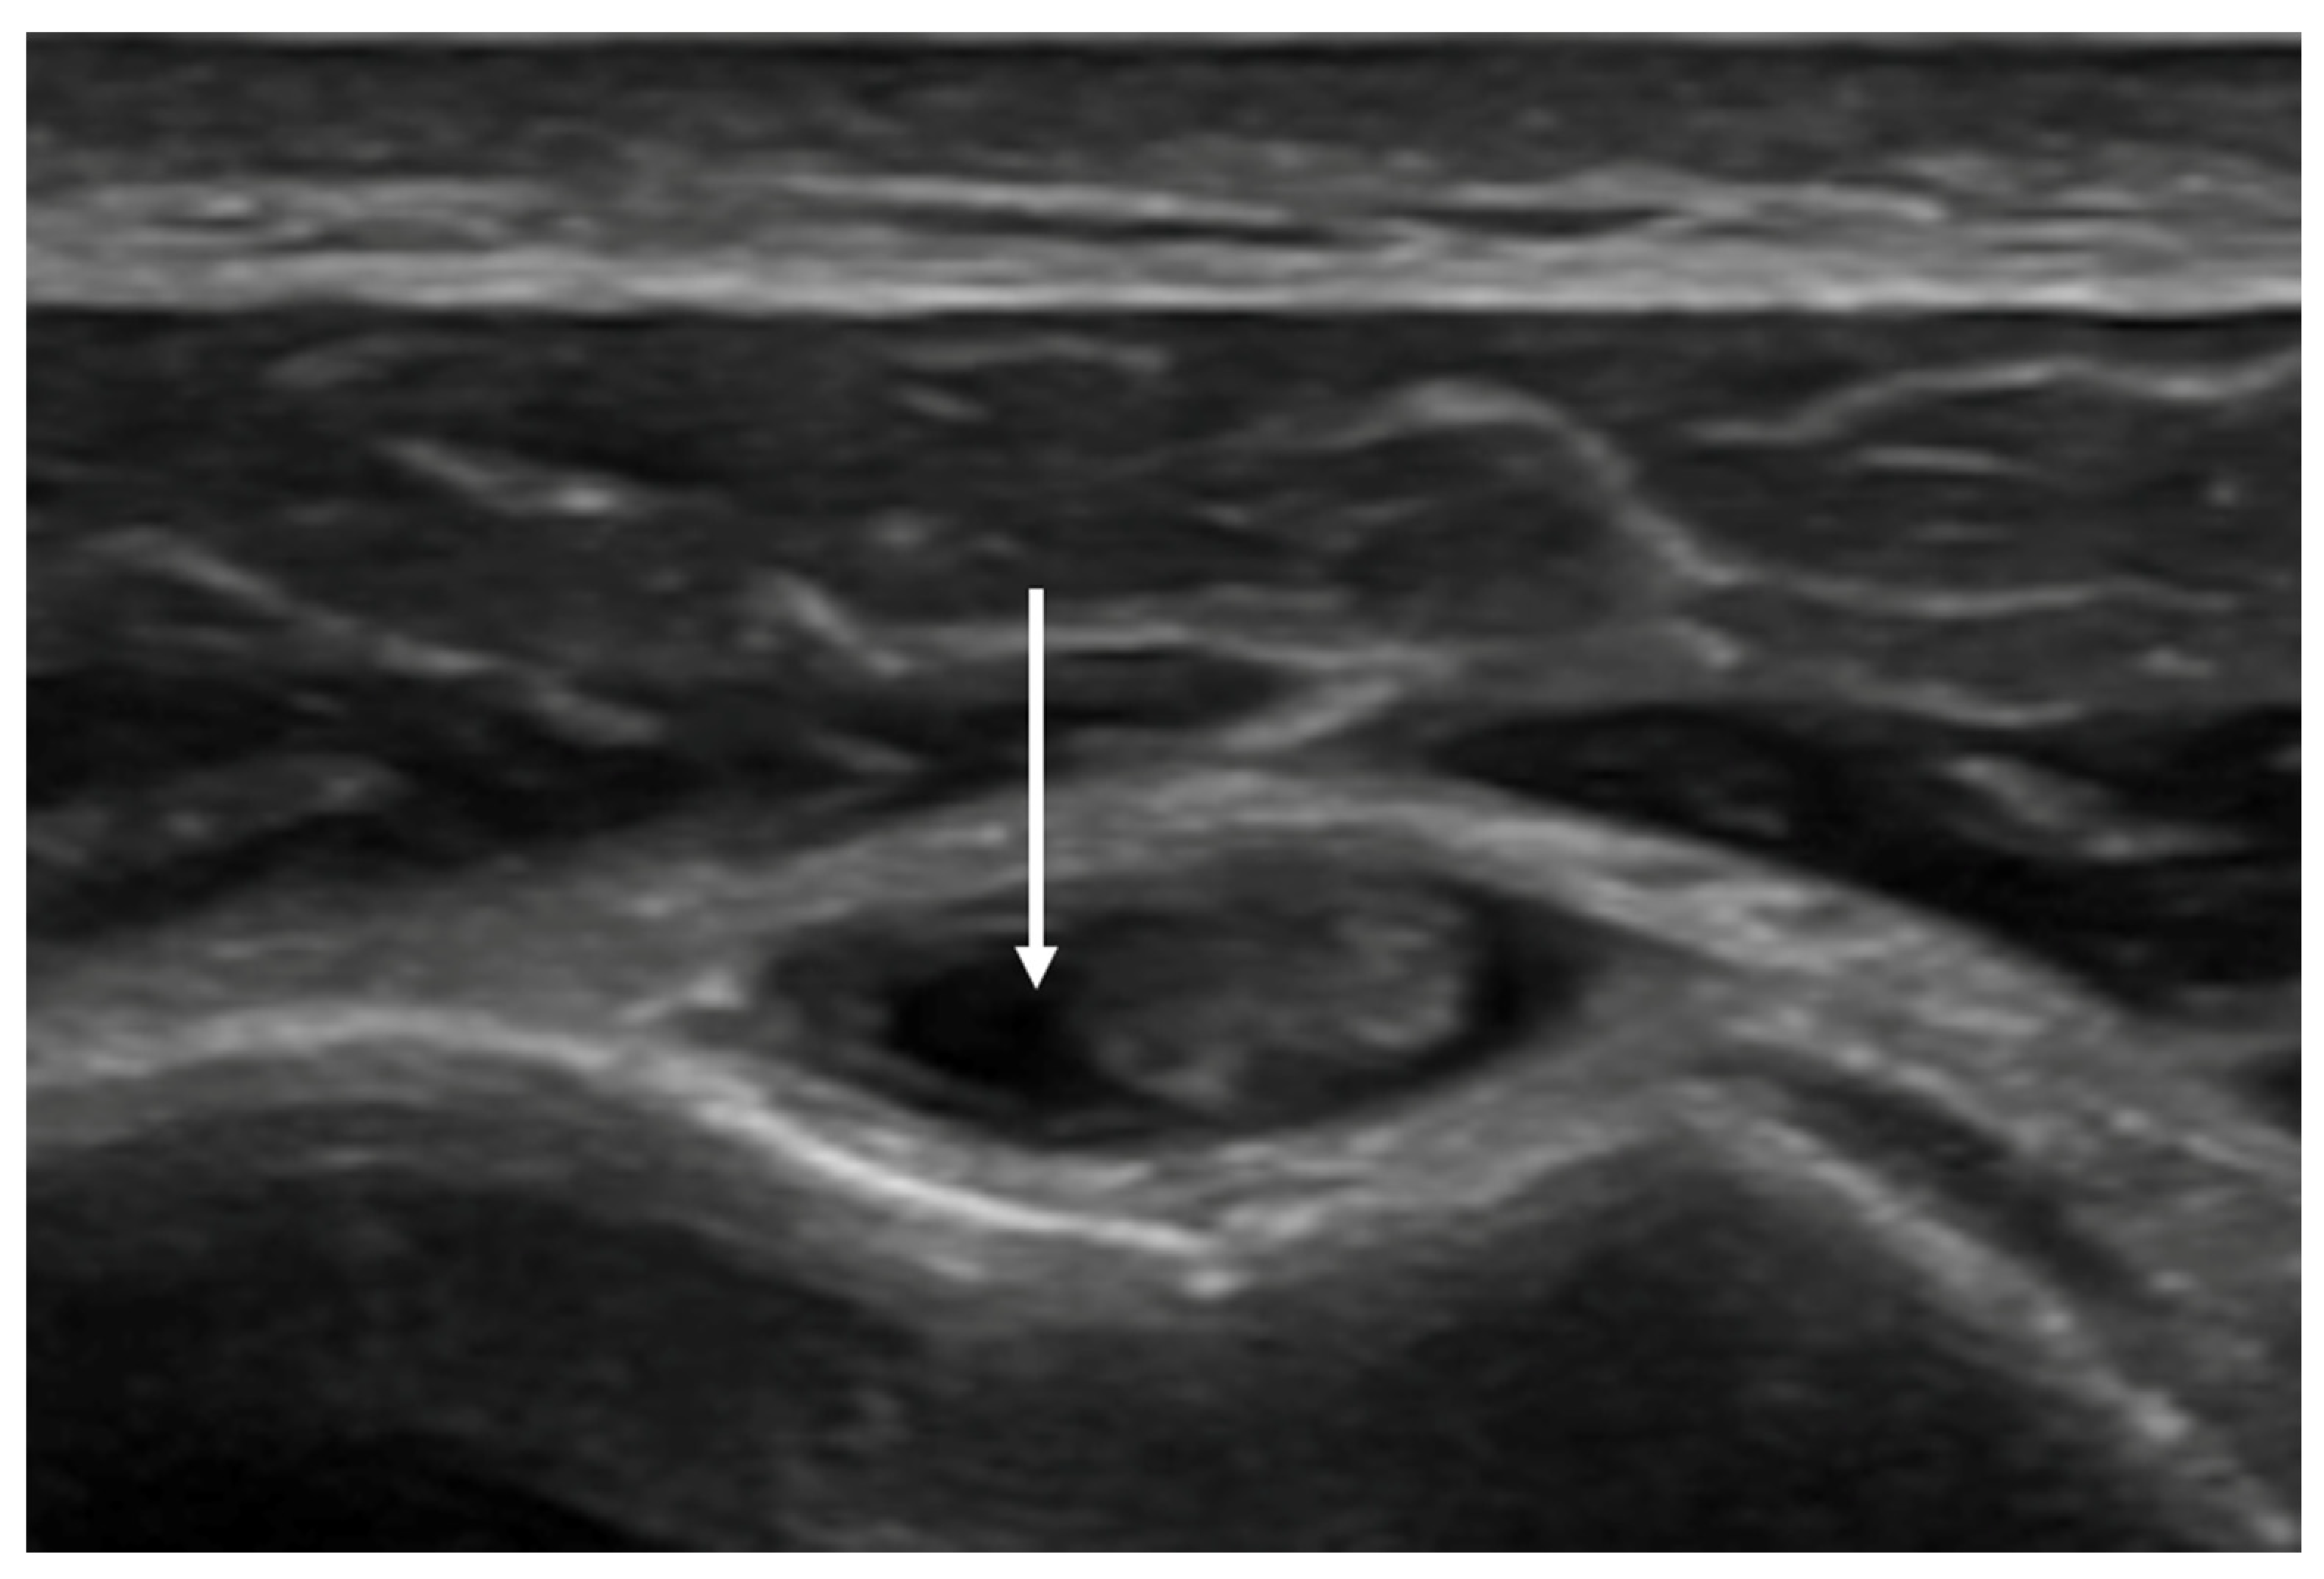

- Effusion within the LHBT sheath: evaluated in the same position of the RI, with the probe placed in the axial plane in the bicipital groove.

3.4. Rotator Interval (RI) Thickness and Effusion within the LHBT Sheath